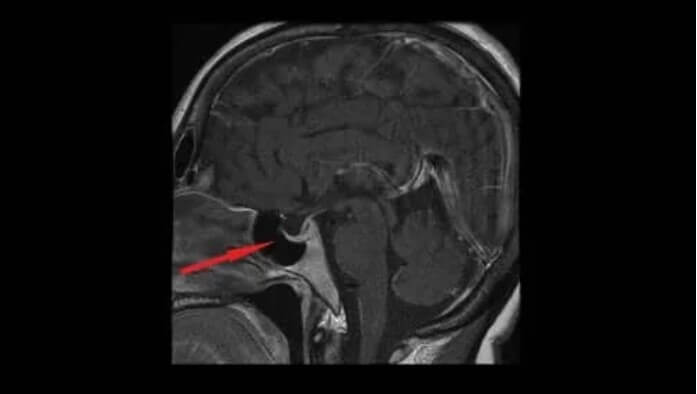

Οι πιο σχετικές εξετάσεις που βοηθούν στην επιβεβαίωση της διάγνωσης είναι το οπτικό πεδίο και η μαγνητική τομογραφία και αξονική εγκεφάλου.